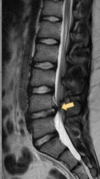

This image shows a herniation at which level L1/L2 L2/L3 L3/L4 L4/L5 L5/S1

**L4/L5**